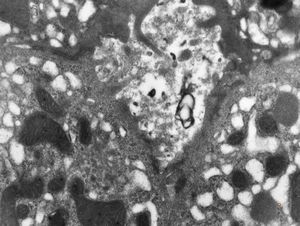

M,19y. | normal hepatocyte